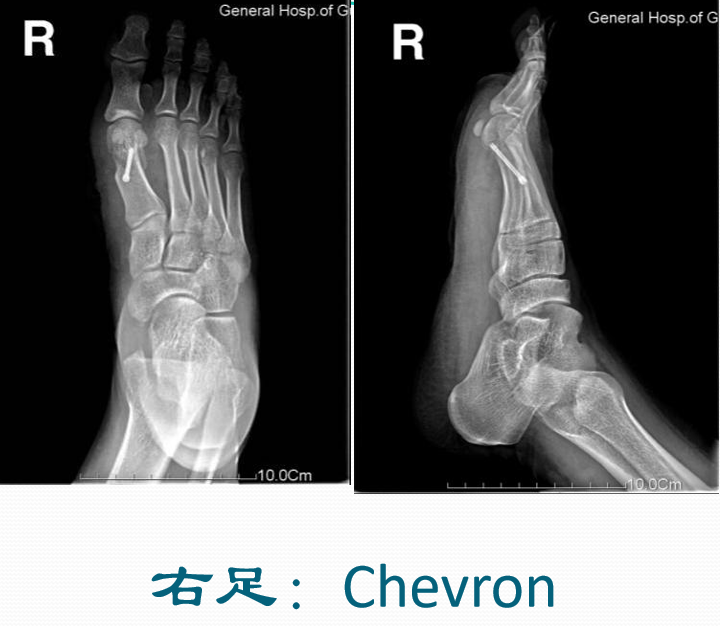

第1跖骨远端Chevron截骨术1.于第1跖骨头内侧作水平位“V”形截骨,开口向近端,截骨后将远端跖骨头向外侧推移3-5mm,切除多余骨质,固定截骨面。2.利用截骨时轴线的变化可以调整跖骨头位置和第1跖骨长度。

典型病例例1:姚X,女,78Y。

Chevron+第二跖骨Weil